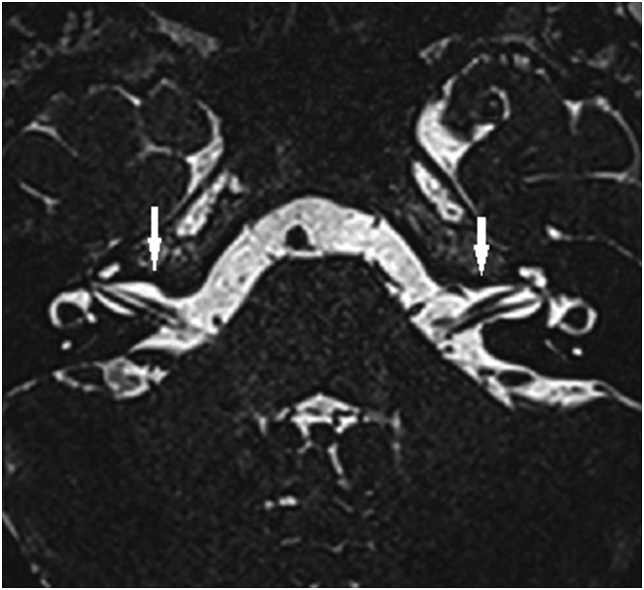

Fig. 1.

Axial three dimensional constructive interference in steady state (3D-CISS) image of the normal-hearing ears of a 24-year-old man at the level of the inner acoustic canals. The courses of both facial and vestibulocochlear nerves in the cerebellopontine angle cisterns and inner acoustic canals are clearly seen (white arrows).